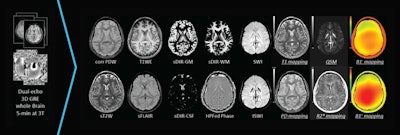

The software allows users to acquire 16 brain contrast images -- including 10 enhanced contrast qualitative outputs and six quantitative outputs -- in five minutes on 3-tesla systems, the company said.